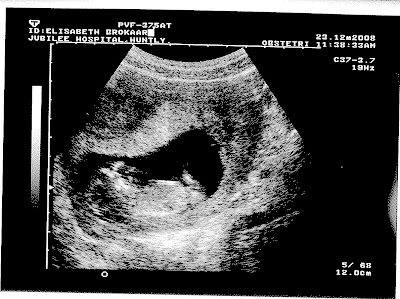

We had our 12 week scan and here are the pictures! My due dates is set for July 1st!!! yeah-everything went well: strong heartbeat, moving around and what a cutie!!! The lady did think that the baby was sucking his/her thumb!!! sweet....